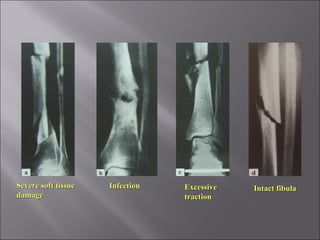

 Fracture takes more than the usual time to unite.

 CausesCauses

 Inadequate blood supply

 Severe soft tissue damage

 Periosteal stripping

 Excessive traction

 Insufficient splintage

 Infection

 Clinical featuresClinical features

 Fracture tenderness

 X-RayX-Ray

 Visible fracture line

 Very little callus formation or

periosteal reaction

Severe soft tissueSevere soft tissue

damagedamage

InfectionInfection ExcessiveExcessive

tractiontraction

Intact fibulaIntact fibula